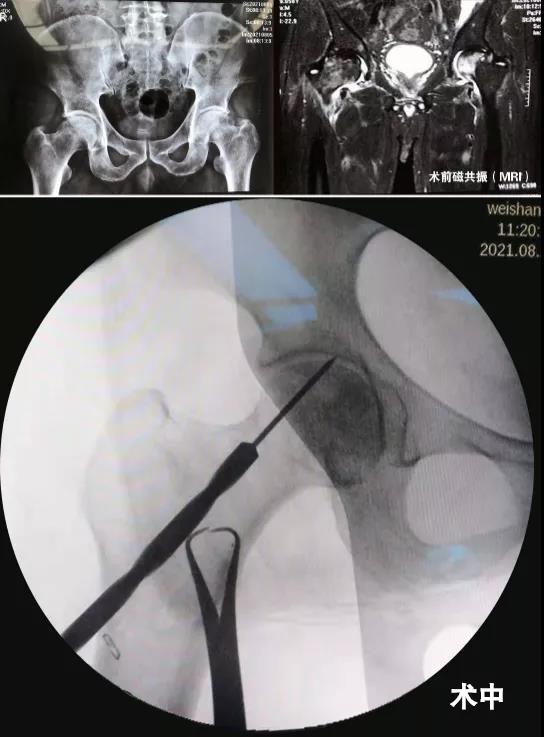

经赵琨主任详细询问病史,并结合影像学检查,确诊为股骨头坏死。赵琨主任向韩先生介绍了目前股骨头坏死早中期的多种保髋治疗方法,并就预后、并发症及相关术后康复锻炼作出详细解答,在与家人经过慎重考虑后,一致同意手术治疗。在赵琨主任主刀下,骨一科团队为其行“双侧股骨头坏死微创减压术”,术中精准减压,手术顺利完成,且创伤小。术后一天,在医生的指导下,韩先生就可以自行活动了。韩先生表示,骨一科的医护人员不仅技艺精湛,为人还很和善,住院期间有啥大事小情,都随叫随到,我们只能用一面锦旗表达内心感谢!

我们根据股骨头坏死的分期不同,根据患者病情“量体裁衣”制定个体化方案,除常规开展微创精准减压治疗股骨头坏死外,对于中末期股骨头坏死即髋关节发育不良导致的继发性股骨头坏死及骨关节炎行全髋关节置换术亦取得了良好的手术效果。